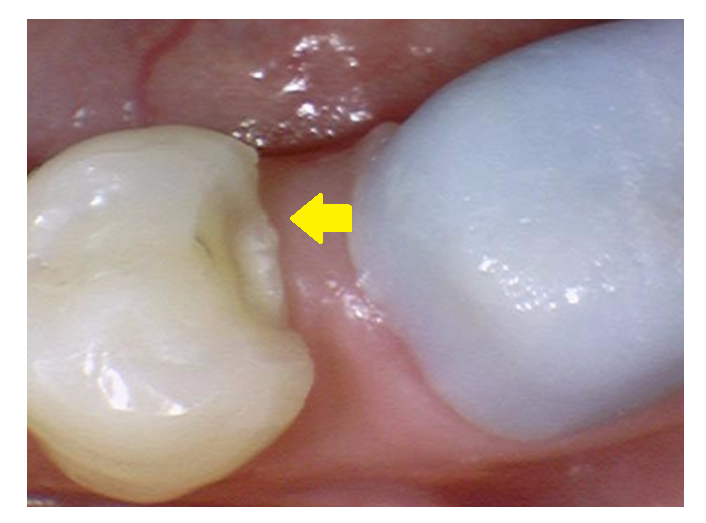

241226 귀퉁이만 깨져 인레이가 필요한 경우

정말 간단할정도로

조각이 떨어져 나간 경우는 다듬어서 쓰는 경우도 있어요.